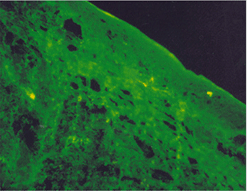

임상증상4

사진38 사진39 사진40

설명38 설명39 설명40